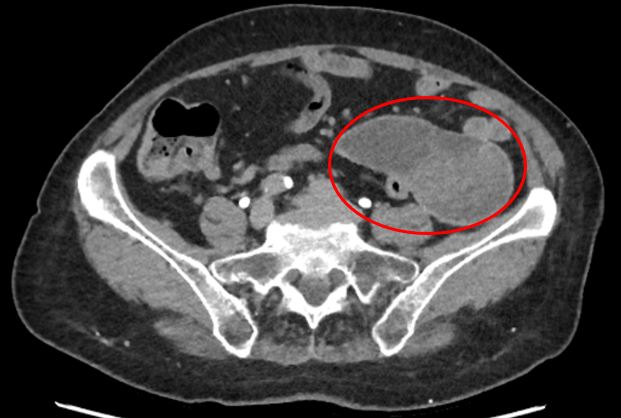

По результатам КТ живота с контрастированием выявлены неорганные образования в брюшной полости, расположенные между петлями кишечника с выраженной фиброзной капсулой, а также состояние после спленэктомии и консолидированные переломы ребер слева. Учитывая анамнез, одним из самых вероятных подозрений стало возможное наличие «инкапсулированных инородных тел».

2. В левом латеральном канале обнаружено и мобилизовано образование 8-10 см также яйцевидной формы, что потребовало мобилизации селезеночного угла ободочной кишки.